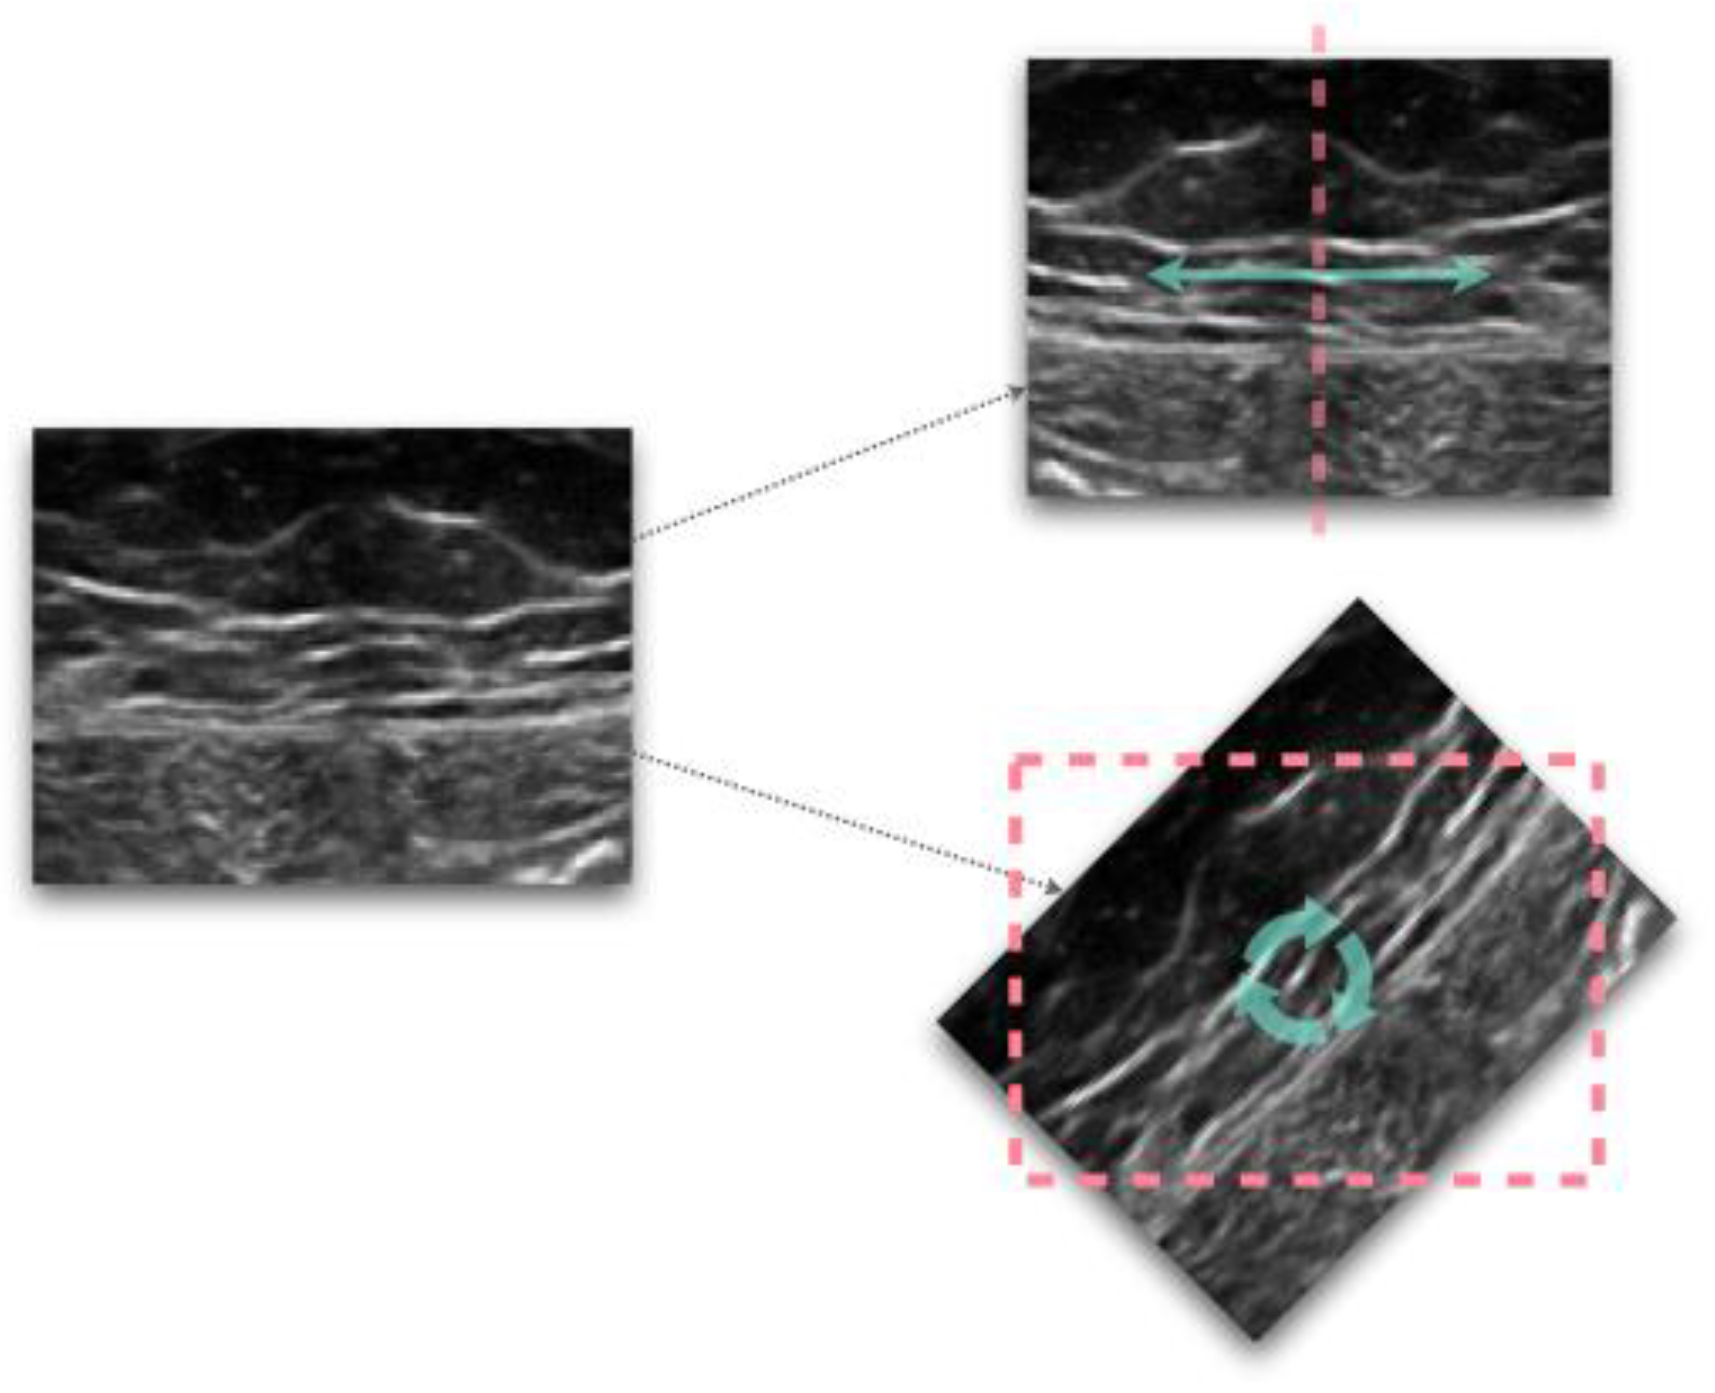

| Normalization/histogram equalization | [1,12,13,15,17,18,19,25,26,28,31,32,33,39,40,55,59,60,61,63,70,73,80,85,86,90,91,104] |

| Intensity-based/dimensional-based filtering | [3,6,12,17,28,54,70,86] |